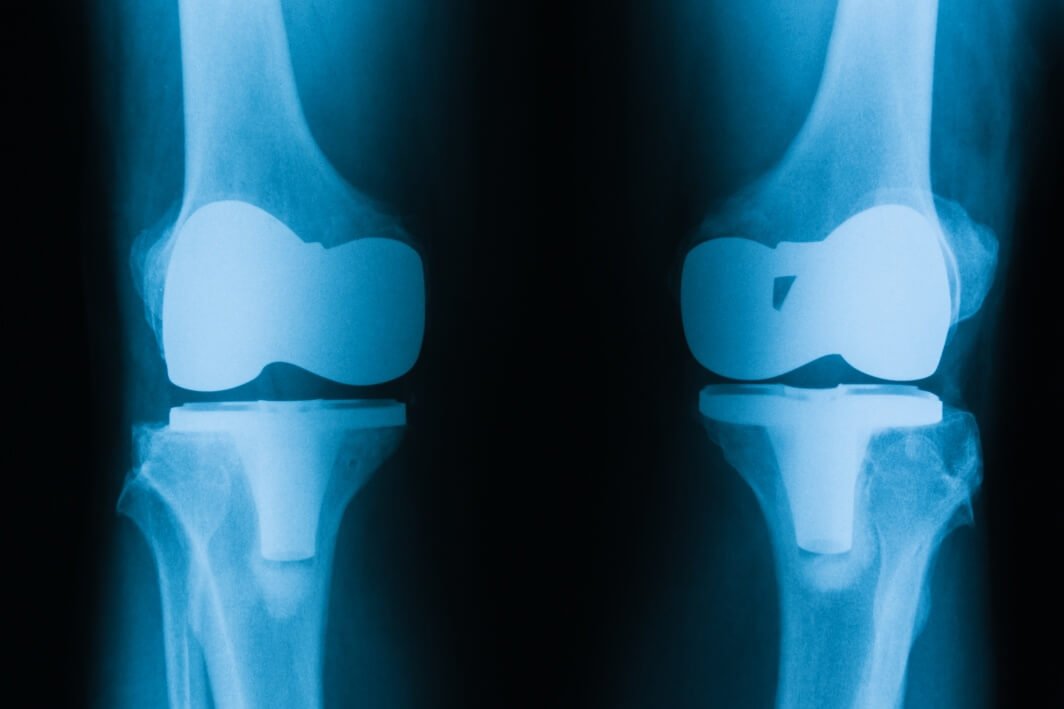

Total Knee Replacement, also known as Total Knee Arthroplasty, is a surgical procedure that involves replacing the damaged or diseased knee joint with an artificial implant, known as a prosthesis. This procedure is typically recommended for patients suffering from severe knee pain, reduced mobility, and limited functionality due to conditions like osteoarthritis, rheumatoid arthritis, or post-traumatic arthritis.

2. Total Knee Replacement Surgery: Our skilled surgeons perform Total Knee Replacement surgeries using advanced techniques and state-of-the-art facilities. During the procedure, damaged bone and cartilage are removed, and the artificial implant is meticulously placed to restore knee function and alleviate pain.